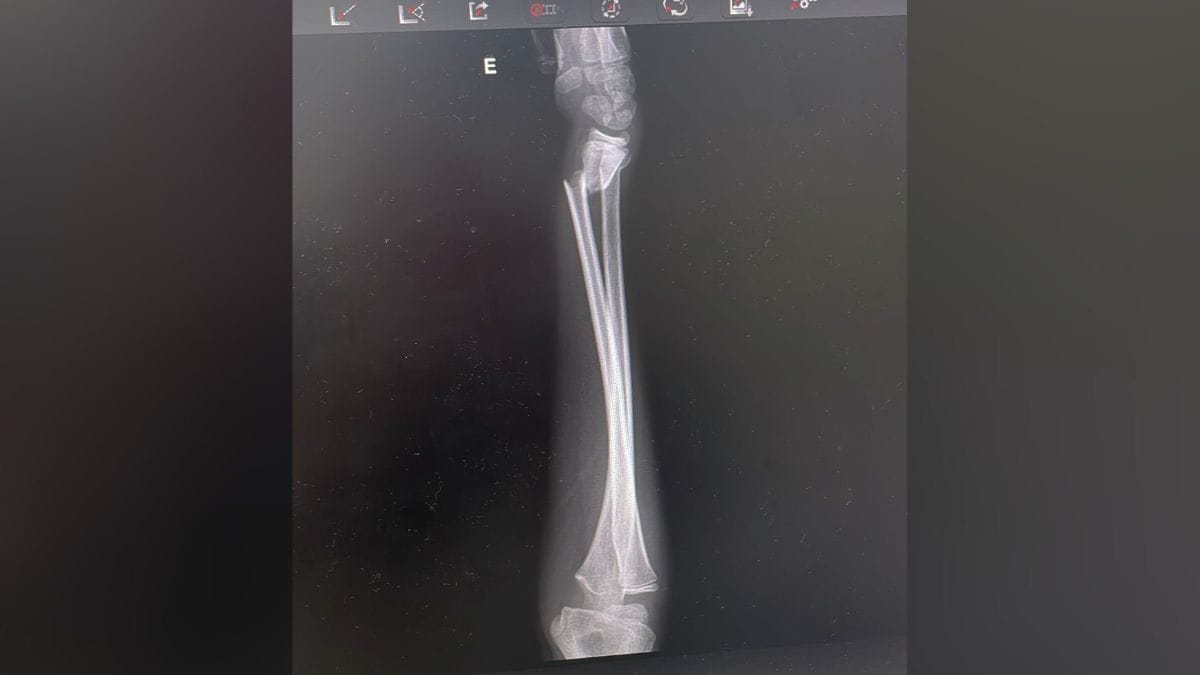

Em situações mais simples, a imobilziação com gesso já é o suficiente para o tratamento. Em casos mais graves, como o caso do menino de Joinville, a criança pode precisar de intervenção cirúrgica.

— O mais importante é que se a criança teve uma queda, [deve-se] realmente levar para uma avaliação médica, para poder radiografar esse membro, porque a criança às vezes também faz fraturas menores e que passam como se não tivesse fratura — comenta.

Como está o menino